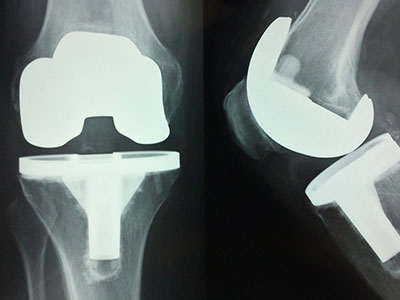

We specialize in advanced Joint Replacement surgeries, including complex primary and revision procedures. Our team also offers expert care in spine surgery, arthroscopy, limb reconstruction, and pediatric orthopedics — all under one roof.

• Advanced Joint Care

Expert orthopedic treatments for joint pain, arthritis, and knee/hip replacement surgery using minimally invasive techniques.

Successful Joint Replacements